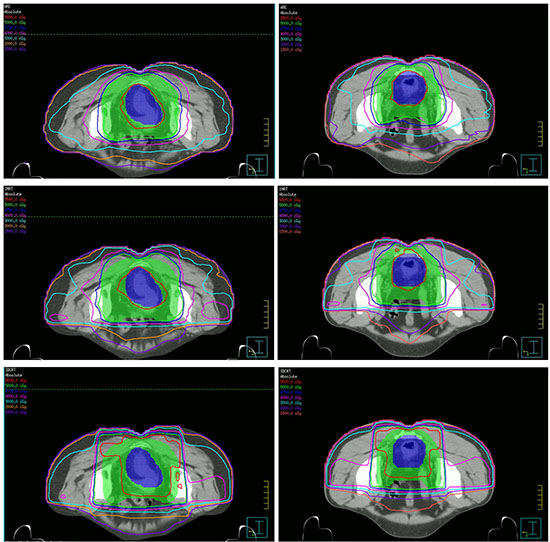

The dose distributions for the three different treatment plans including 3DCRT, IMRT and SmartArc in the axial slices of two patients were shown in the Figure 1. The isodoses were set from 15–55 Gy. The PTV-C was outlined as a green area in all images and the PTV-G was shown as the blue area. The average cumulative DVHs of the ten patients for the PTV-C, the PTV-G, the OARs (bladder, small bowel and femoral heads) and normal tissues were calculated and plotted in Figure 2. The statistical dosimetric evaluation and comparison of the three planning techniques were listed in Table 1.

Figure 1: Dose distributions of three planning techniques for two patients in the axial slices. From up to down are SmartARC, IMRT and 3DCRT respectively.